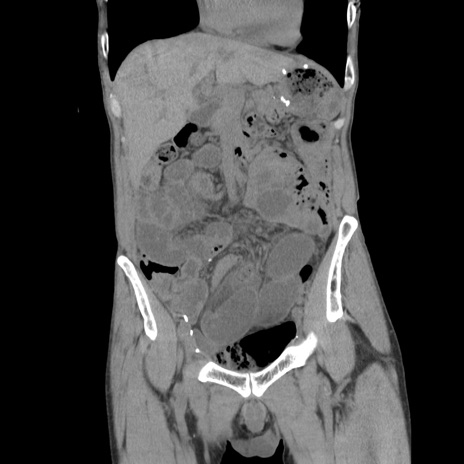

横断像

【症例】 60歳代男性

【主訴】 下腹部痛

【現病歴】 本日夜中より下腹部痛の症状認め、受診。

【既往歴】 膀胱癌(膀胱全摘+尿管皮膚瘻術) 、胃癌術後

【身体所見】 BT 35.3℃、PR 58/min、BP 136/98mHg、腹部平坦、軟、腸蠕動音±、ストマ留置あり、左上腹部~正中部に圧痛あり、反跳痛なし。

【データ】WBC 5100、CRP0.01